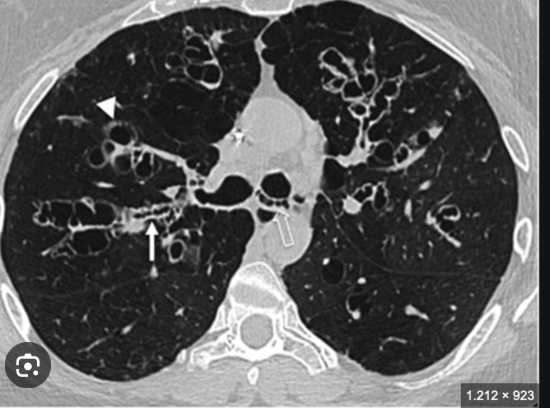

Que imagen distingue distribución en EPOC enfisematoso?

TC

Centrolobulillar

Paraseptal

Panlobulillar